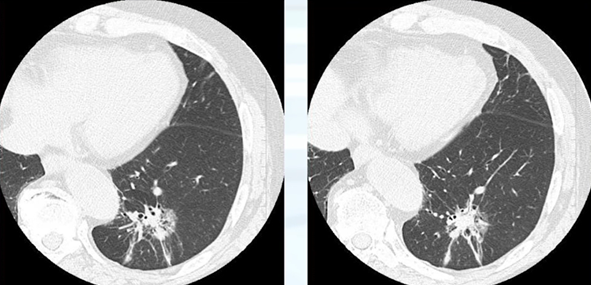

■CT所見

CTでは胸膜陥入像が確認でき、限局したすりガラス影が確認できます。このような肺癌の多くは肺腺癌です。肺腺癌は内部に線維化を伴って胸膜を引っ張り込んでいくことが特徴です。